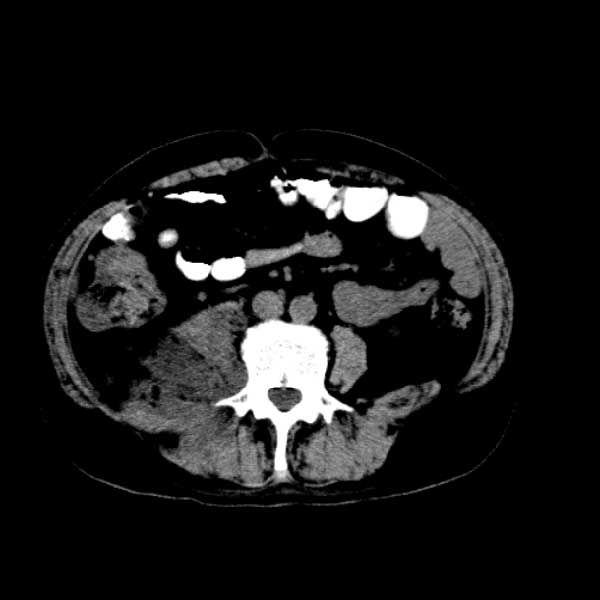

标题: CT13513:男 71 腹部疼痛20余天,近几天高热就诊,骨窗未见异 [打印本页]

标题: CT13513:男 71 腹部疼痛20余天,近几天高热就诊,骨窗未见异

考虑感染性病变可能性大,起源于阑尾?

感染,脓肿形成

考虑为化脓性阑尾炎.脓肿形成.及多肌肉累及.

考虑右侧腰大肌脓肿,向右髂窝、右腹股沟流注。

支持化脓性阑尾炎伴右髂窝脓肿、腰大肌腰方肌脓肿形成。

考虑腹腔及盆腔化脓性炎症,累及右侧髋关节及腹股沟区.

首先考虑化脓性阑尾炎伴腰大肌、腰方肌脓肿,不除外回盲部结核。

回盲部癌待排除。

患者肠镜检查考虑结肠癌,病理证实

患者肠镜检查考虑结肠癌,病理证实。肺部ct可见多发结节,考虑转移